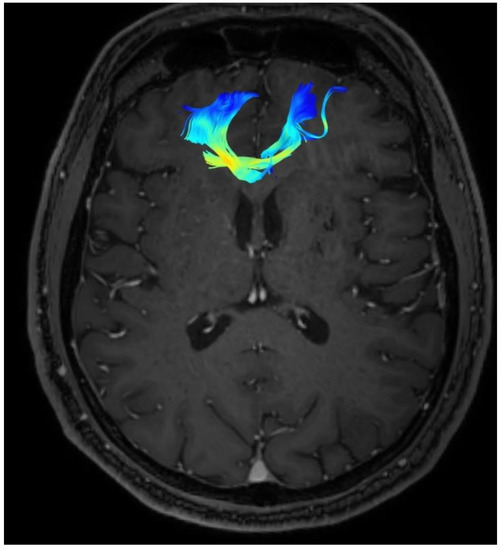

In the presented case, the analysis covered forceps minor and arcuate fasciculus. The following parameters were used for the purpose of the evaluation: FA, ADC, MD, and the number of fibers. The parameters were measured immediately before the procedure and six months after the cingulotomy. Their exact values are presented in Table 1 and Table 2.

Based on the collected results, after 6 months follow up, an increase in the FA value of both the forceps minor and both the arcuate fasciculus was noted. Moreover, an increase in the number of fibers was observed in each analyzed structure, compared to the initial results.

Changes in the anatomy of forceps minor before and after cingulotomy are presented in Figure 2 and Figure 3; moreover, arcuate fasciculus before and after cingulotomy is presented in Figure 4 and Figure 5.

In addition, we observed a decrease in the apparent diffusion coefficient—the ADC parameter, in both examined structures compared to the value before neuroablation. We also noted that there was a reduction in the MD parameter after cingulotomy.

Figure 5. Arcuate fasciculus after cingulotomy.

Brainsci 13 00044 g005